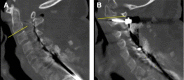

Methods: C2 pedicle screws were inserted using a fluoroscopically assisted freehand technique. Independent fellowship-trained spine surgeons blindly reviewed intraoperative fluoroscopic and postoperative computed tomography (CT) images for evidence of facet joint penetration (FJP). C2 pedicle morphometry, the sagittal angle of the facet joint, axial and sagittal pedicle screw angles, and screw length were measured on the relevant CT images.

Results: A total of 34 patients fulfilled the study criteria, and a total of 68 C2 pedicle screws were placed. Eight screws (16%) penetrated the C1-C2 facet joint. The mean sagittal angle of the C1-C2 facet joint was significantly lower in the FJP group compared with the non-FJP group. The mean sagittal angle of the screws was significantly higher in the FJP group compared with the non-FJP group. The mean screw length was significantly greater for screws causing FJP compared with the non-FJP group. The mean axial screw angle was significantly lower in the FJP group compared with the non-FJP group. Pedicle width, length, height, and transverse angle were not significantly associated with FJP. Independent reviewers were able to identify FJP on intraoperative fluoroscopic imaging in 2 out of 8 cases.